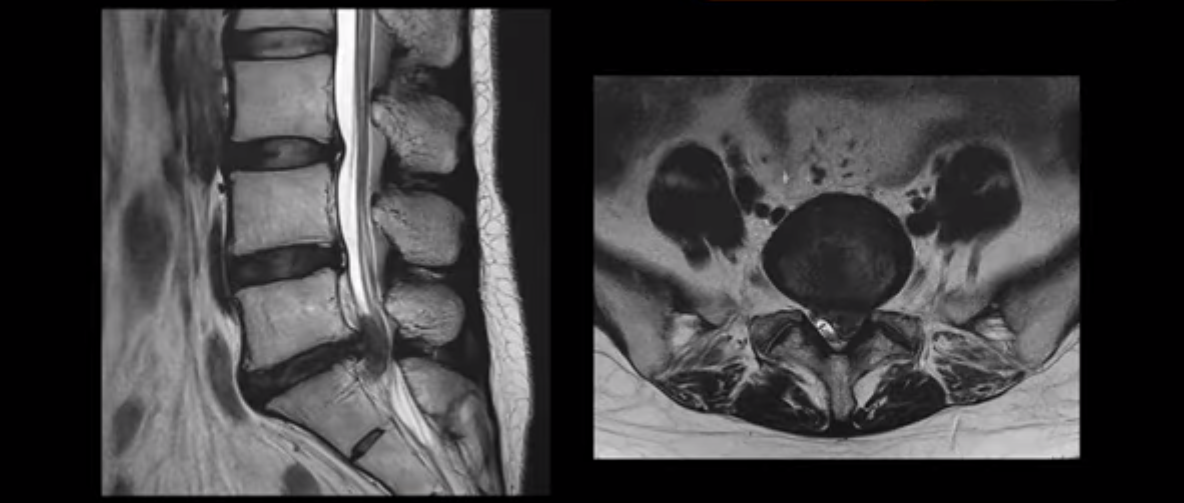

허리디스크 보존치료 좀 경험했다는 환자분들이 자기 경험으로 빗대어 방사통은 원래 오래 가는 것이 당연한 것처럼 말하는 경우가 많습니다. 그런데 저희 같은 비수술 척추치료를 전문적으로 10년 이상 수만 명씩 하고 있는 병원의 입장에서 보면 매우 답답하고 안타깝습니다. 그럼 이 4주 얘기가 파열이 심하지 않은 환자 얘기인지 궁금하실 텐데, 전혀 아닙니다. 여기 보는 MRI처럼 이 정도로 파열이 심하고, 심지어는 마비까지 있는 사람들의 이야기입니다. 이런 사람들이 최적화된 조건 하에서 평균 4주면 방사통이 가라앉는 것입니다.